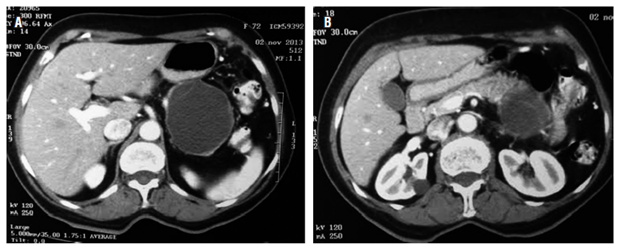

La paciente es una mujer de 73 años remitida de un hospital de III nivel, con historia de dolor abdominal difuso severo de 1 año de evolución resistente a múltiples esquemas de analgésicos y emesis intermitente. Síntomas constitucionales y antecedentes de pancreatitis negativos. No hay presencia de masas o ascitis en el examen físico. El hemograma, bilirrubinas, transaminasas, fosfatasa alcalina, amilasa, lipasa y marcadores tumorales en sangre (antígeno carcinoembrionario [ACE] y antígeno carbohidrato [Ca] 19-9) fueron normales. La TAC abdominal contrastada evidenció una lesión redondeada quística septada bien delimitada en cuerpo y cola del páncreas de 54 x 40 x 60 mm (Figura 1).

Cualquier quiste pancreático mayor de 1 cm debe caracterizarse por TAC de abdomen o RM abdominal con gadolinio. La apariencia tomográfíca de las NQM es variable, pueden ser similares a los pseudoquistes o los cistoadenomas serosos. Son uni o multiloculadas, y macroquísticas (>2 cm). El contraste realza las paredes quísticas, lo que permite identificar septos o excresencias sólidas (Figura 1B) 1. El compromiso hepático y peritoneal y la invasión local deben descartarse 10.